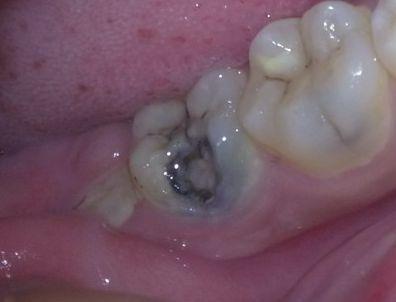

对于蛀牙,我们通常采用填充的方式. 如果蛀牙到达牙髓的神经,则采用根管治疗消除炎症,然后戴上牙套.

如果不及时治疗,龋齿会变得越来越大,从浅龋变到深龋,对食物刺激(例如酸辣糖醋)很敏感;当损伤到达牙髓,引起牙髓炎时,牙痛将变得非常严重. 当病变进一步发展时,会引起根尖性牙周炎牙齿烂个洞,根尖周脓肿,甚至颌骨骨髓炎和牙齿脱落. 龋齿和牙齿脱落会影响咀嚼,增加胃肠道负担并影响健康.